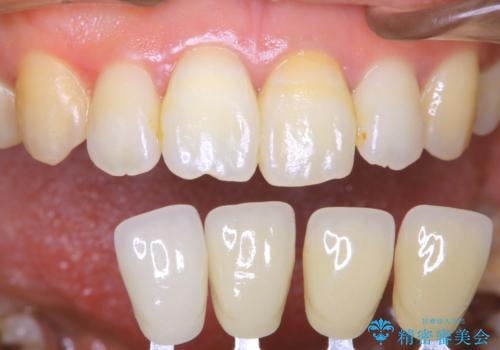

- 前歯の色が気になるとのことでご相談にいらした患者様です。診断の結果、前歯は2本とも失活していたために精密根管治療から治療を開始しました。根管治療後にウォーキングブリーチを行うことで歯の色をトーンアップさせました。患者様より周囲の歯も全体的に白くしたいとのご希望があったため、オフィスホワイトニングも併せて行いました。

ウォーキングブリーチ法とは歯の中に薬剤を入れて内側からホワイトニングを行う方法であるため、根管治療がされている歯のみ適応となります。生活歯(神経が生きている歯)に対してはオフィスホワイトニングやホームホワイトニングが有効です。